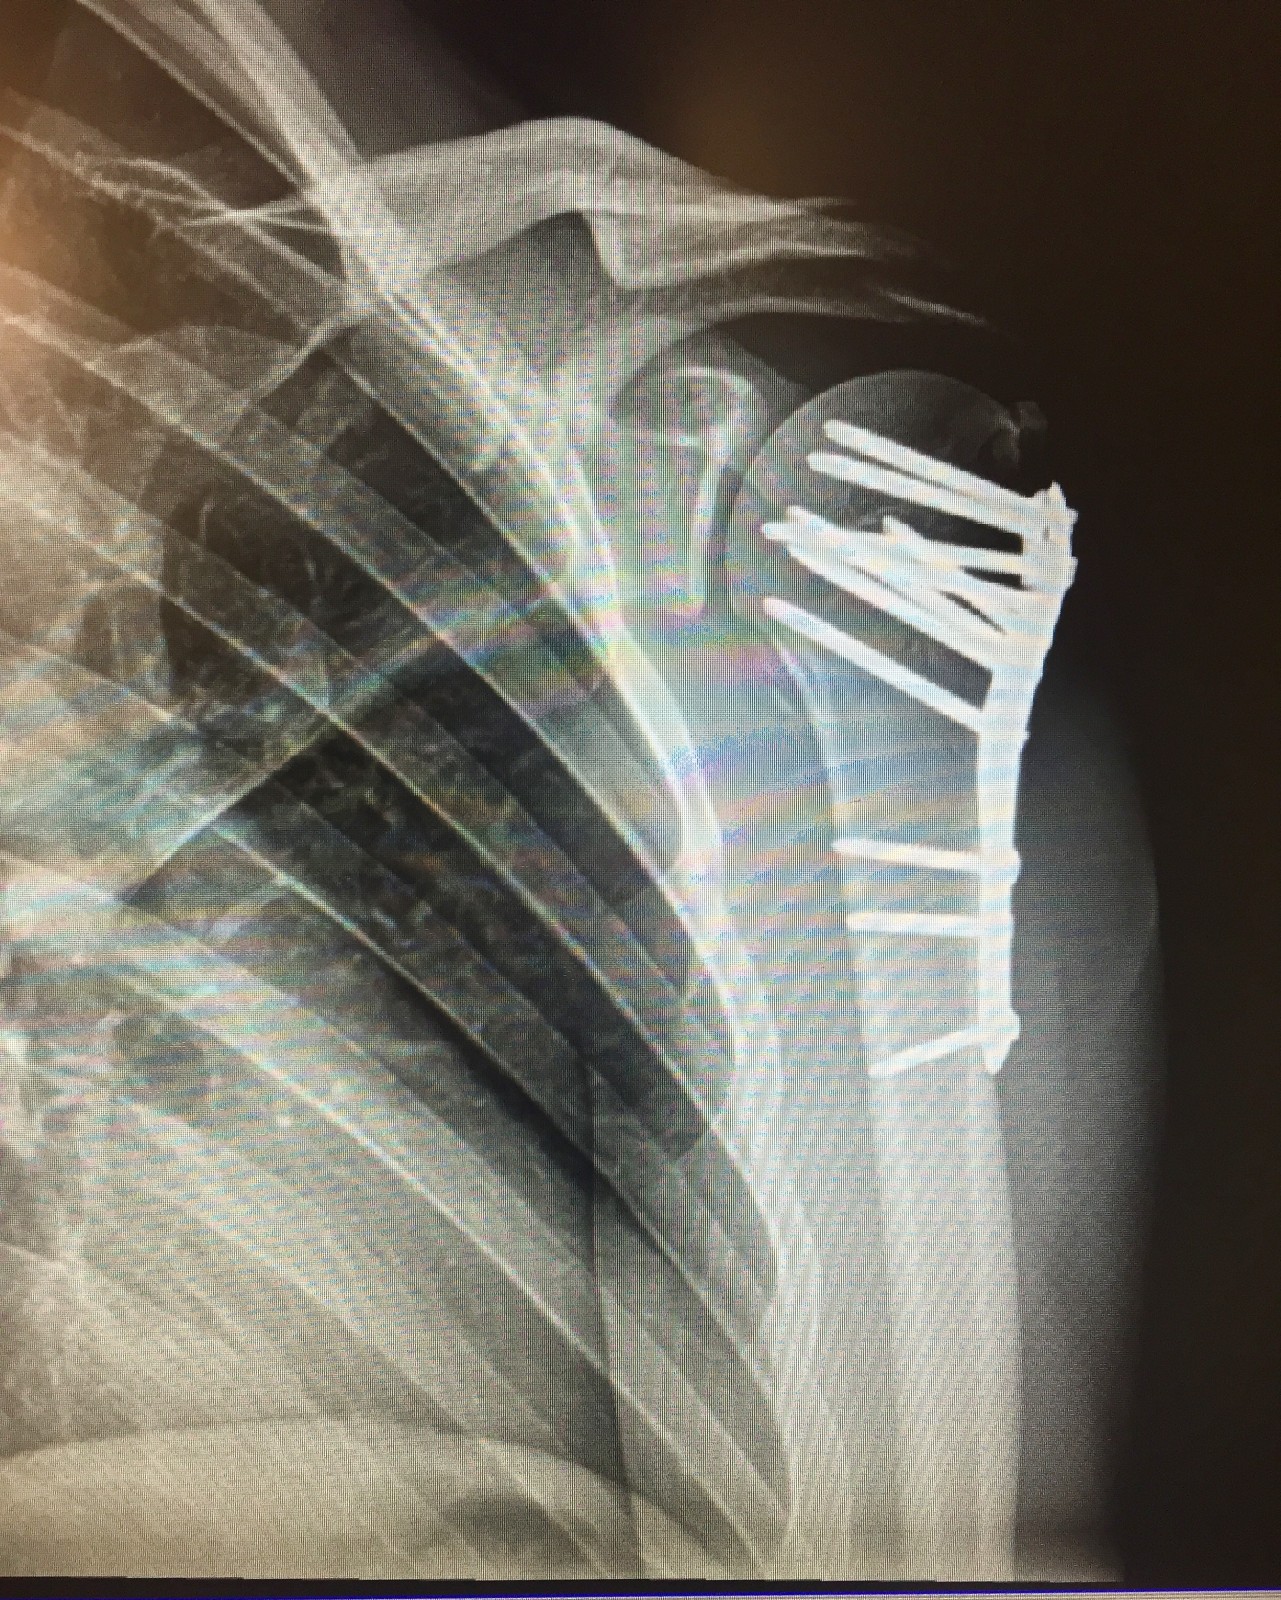

I’ve been a little silent these past few weeks with a broken wing sustained at Glen Helen the Thursday before World Vets. I was doing a shoot/ride day of everyone practicing when, during my own moto, I tucked the front going into a left-hand turn and wrecked my shoulder. I somehow managed to dislocate my shoulder, break the head of my humerus off, break my collarbone, break my shoulder, and tear my rotator cuff. Whoops.